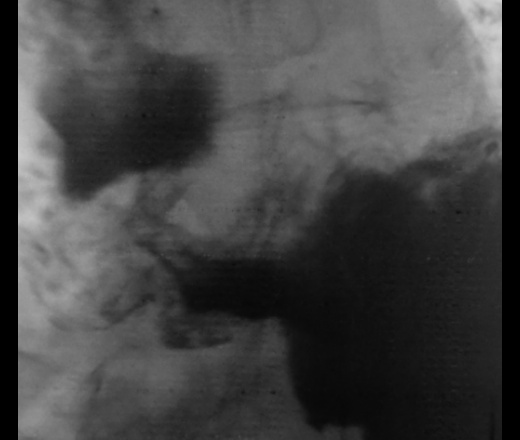

C-r антрального отдела не вызывает сомнений.

С переходом на пилорический же?

Пациент прооперирован в ООД.